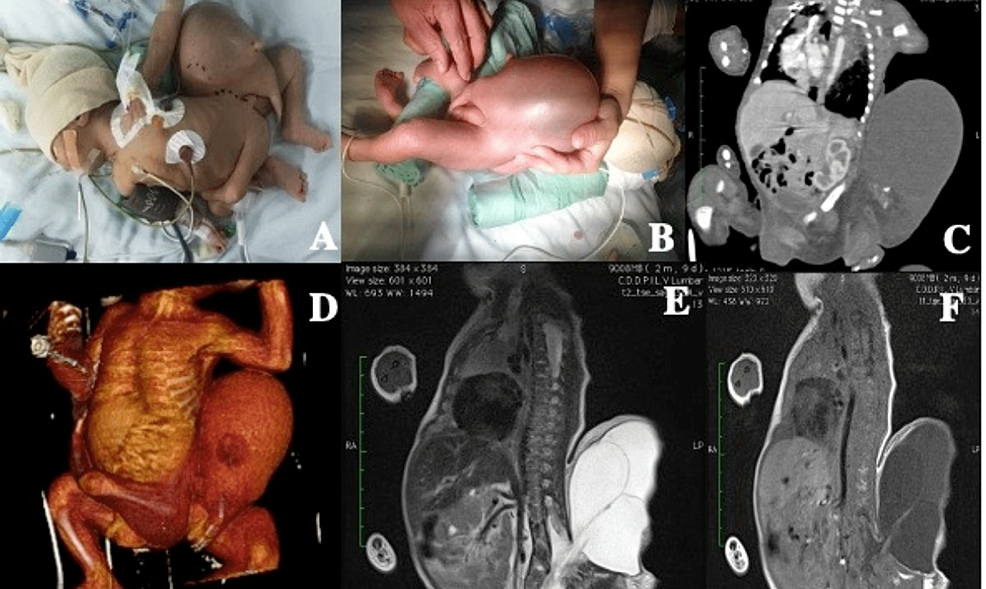

Baby in Baby Gallery Baby in Baby By Nicole Angemi|2025-08-14T10:18:16-04:00January 18th, 2023|The Gross Room, MEDICAL, Pregnancy, Congenital Anomaly| Read More 18